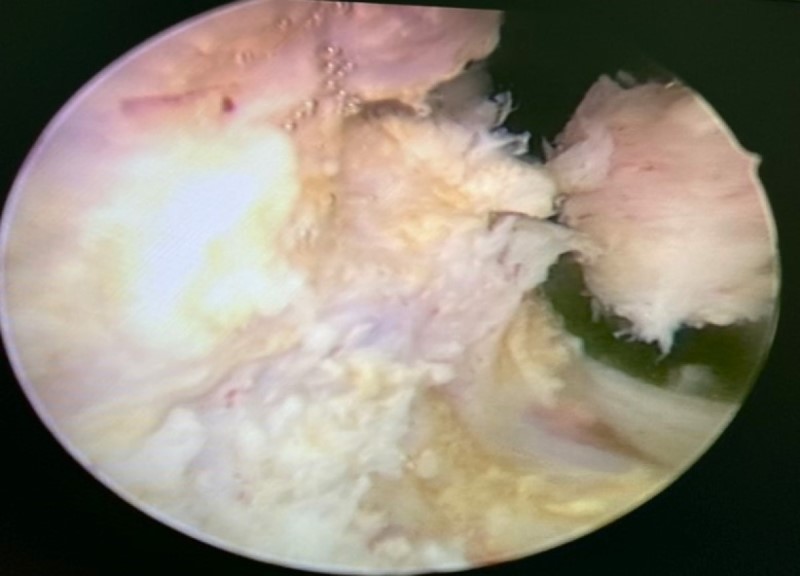

환자는 거의 반 킬로그램에 달하는 전립선 종양으로 인해 심각한 감염 상태로 입원하여 혈뇨를 보였습니다.

하이퐁에 거주하는 77세의 환자 P.V.S,는 수년 동안 전립선 비대증을 앓아왔습니다. 그는 병이 수술이 필요하다는 것을 알았지만 여러 번 지연시켰습니다. 소변에서 혈액이 나오고 눈 감염이 심각한 눈병에 걸린 후에야 병원에 입원하여 정상 크기(20-30그램)의 20배 이상 60세 이상에서 흔히 볼 수 있는 심각한 비대증의 6배인 484g의 전립선 종양이 발견되었습니다.

종양이 미골격 전체를 차지하기 때문에 수술팀은 복잡한 지혈을 위해 미골격을 광범위하게 박리해야 했습니다. 몇 시간 후 미골격 수술은 성공했습니다. 5일 후 환자는 잘 회복되었고 곧 퇴원할 예정이었습니다.